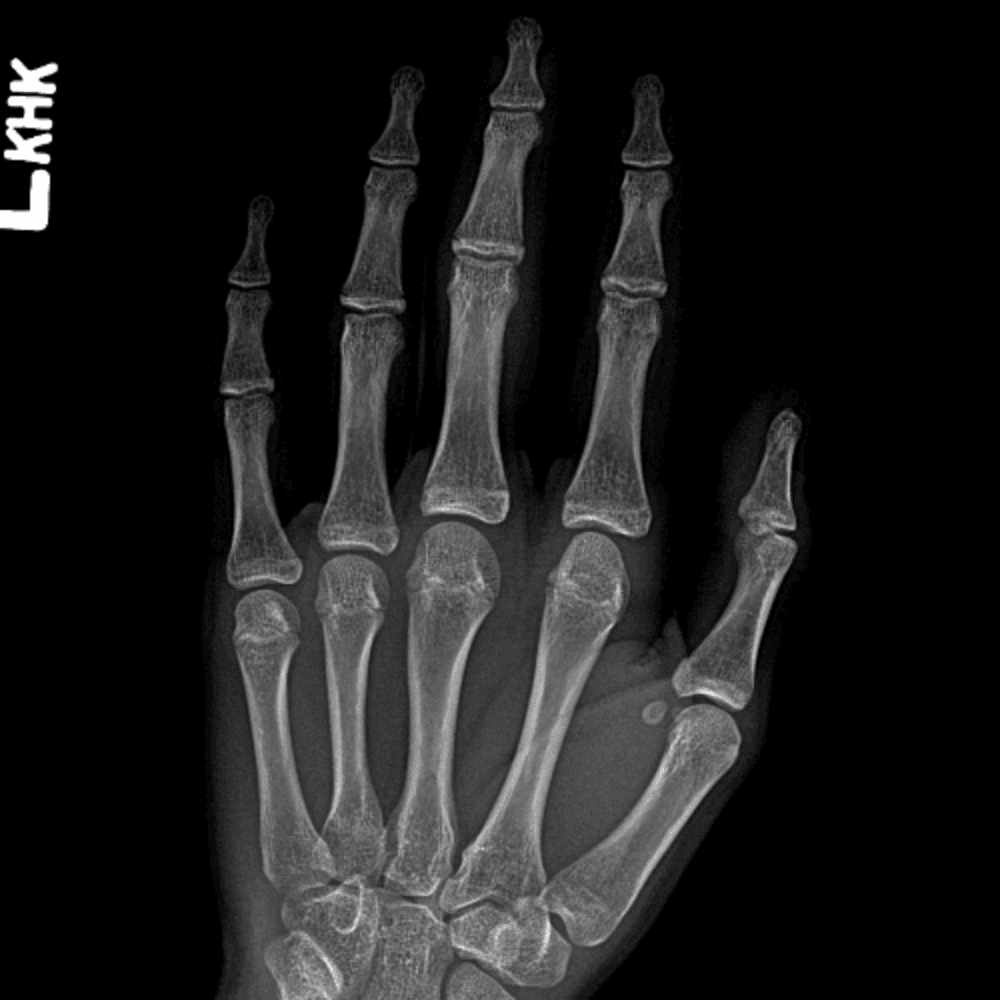

Simulates call by including subtle or difficult cases and some normals.

30 cases